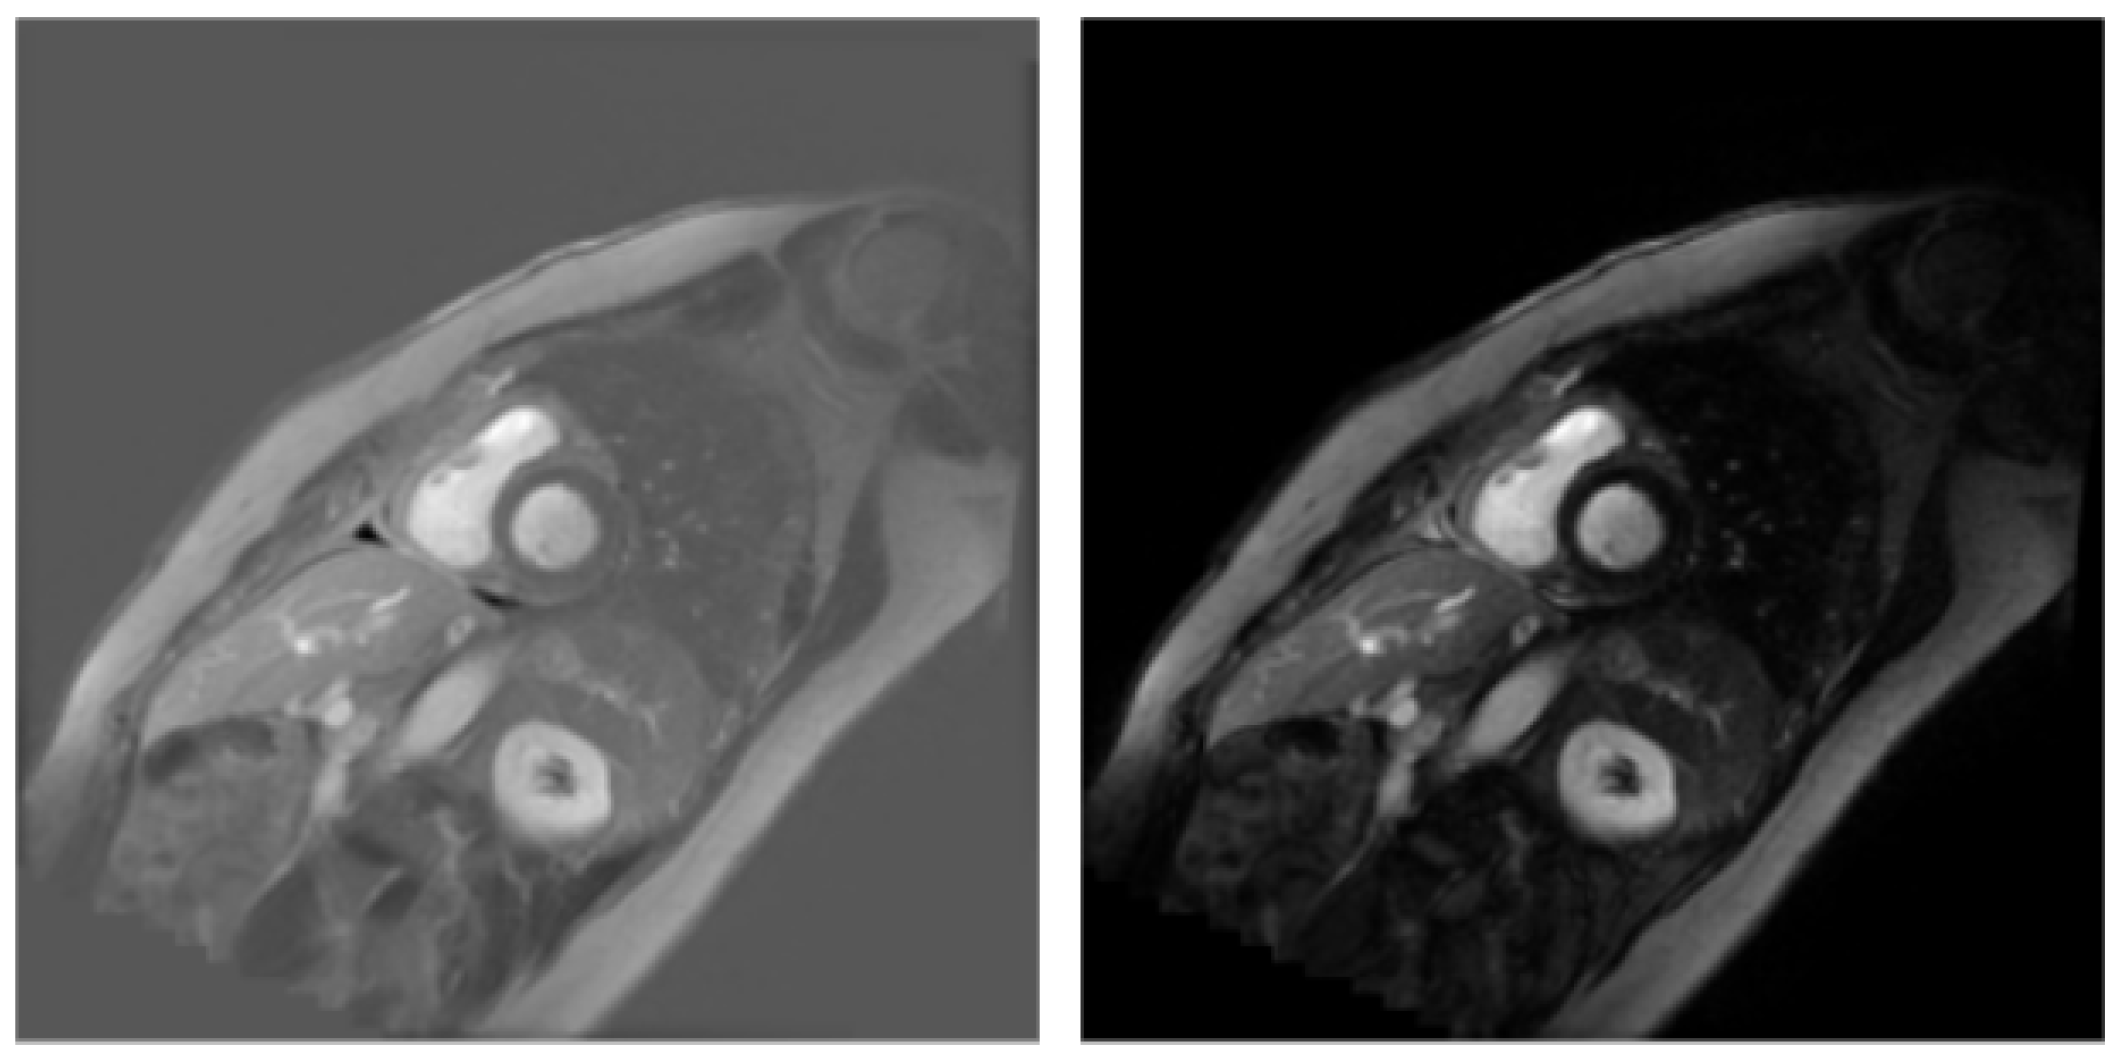

3.1. Dataset